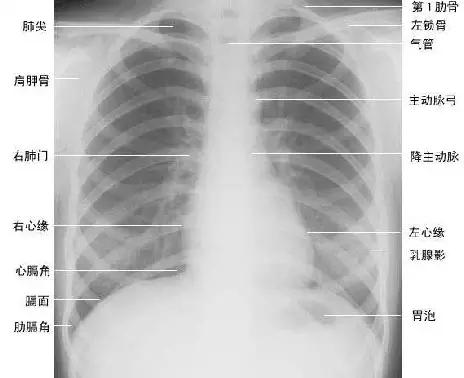

临床拍标准的胸部正位片其实是后前位片,如上图

正常胸部后前位片

② 软策划结构:胸锁乳头肌、锁骨上皮肤皱褶、胸大肌、女性乳房 / 乳头